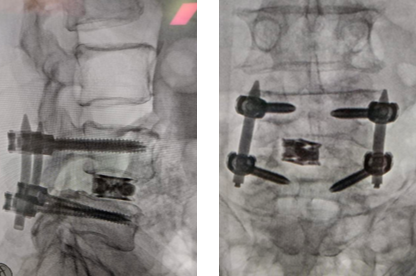

After Surgery Results

Transforaminal Lumbar Interbody Fusion – performed from the back through a small opening, allowing access to the disc space with minimal disruption to spinal structures.

The surgeon removes the damaged disc or diseased bone, places a cage or bone graft between the vertebrae, and secures it with screws and rods. Over months, the bones heal together naturally. The surgical approach (front, back, or side) depends on the patient's specific condition and body type.